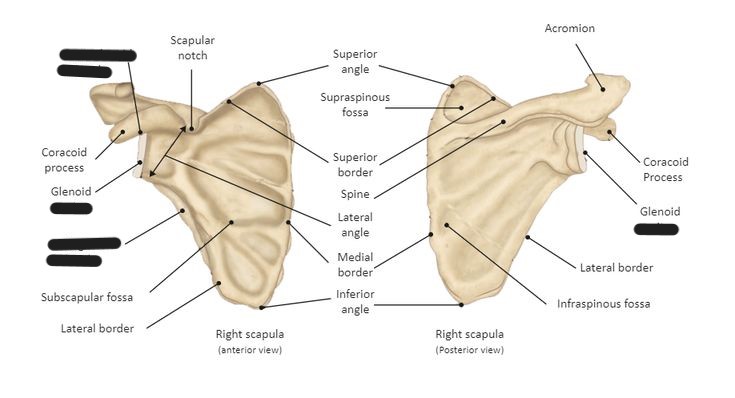

What kind of bone is the scapula classified as?

flat bone

Explain the location of the scapula

lies in the superior, posterior aspect of the thorax

goes from the 2nd to the 7th rib

sits at a 30-45o angle

What is the anterior surface of the scapula called?

costal surface (comes in contact with the ribs)

What is the posterior surface of the scapula called?

dorsal surface

The scapular spine/crest divides the dorsal surface of the scapula into what 2 portions?

infraspinous/infraspinatus fossa

supraspinous/supraspinatus fossa

What is another term for the medial border of the scapula?

vertebral border

What is another term for the lateral border of the scapula?

axillary border

Which border of the scapula is thicker, medial or lateral?

lateral

What makes up the superior angle of the scapula?

junction of superior and medial borders

What makes up the inferior angle of the scapula?

junction of medial and lateral borders

What vertebrae does the inferior angle of the scapula correspond with?

T7

What is located at the lateral angle of the scapula?

head (glenoid) and neck of scapula

What is the coracoid process of the scapula?

fingerlike process extending anteriorly from the scapular notch

What is the acromion process of the scapula?

posterior flattened oval process at the lateral end of the scapular spine

What is the scapular notch?

prominent indentation along the superior border of the scapula

What is the glenoid fossa?

the head/neck of the scapula (point where humeral head articulates with scapula to form the scapulohumeral/glenohumeral joint)

What is the name of the fibrocartilage rim attached around the margin of the glenoid cavity of the scapula?

glenoid labrum

Label the scapula (and determine whether it is a right or left)

Label the scapula